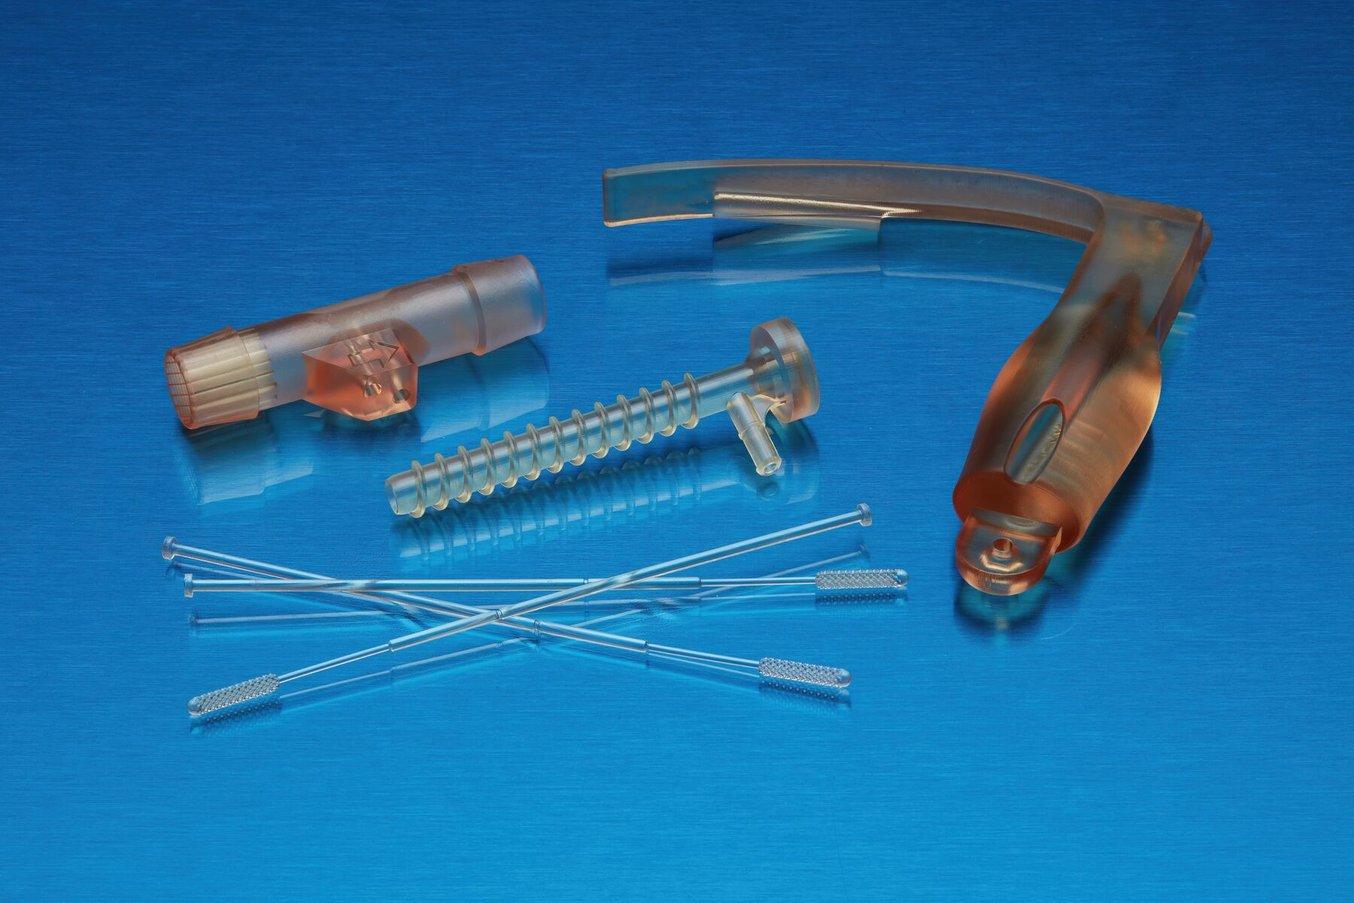

4. Specimen Collection Devices

Puritan Medical Products in Maine, and Copan Diagnostics in Italy, two major suppliers of nasopharyngeal swabs, could not keep up with demand as COVID-19 swept across the world in 2020. nnovators at the Morsani School of Medicine at the University of South Florida turned to 3D printing to help fill the resulting supply chain gap.

They, in conjunction with Northwell Health and Formlabs, designed the first mass-produced 3D printed specimen collection swab. The swabs were printed on the Form 3B using a semi-rigid biocompatible resin. To date, over 40 million COVID-19 test swabs have been 3D printed across sixty different countries.

To drive home the impact 3D printing has had, in early 2023, USF Health, Northwell Health, and Formlabs were recognized by the US Patent and Trademarks Office with a Patent for Humanity award. With the advent of 3D printed biocompatible materials, there has been an increase of medical professionals directly 3D printing specimen collections devices. These could be holding containtors, or swabs. The 3D printing of COVID-19 swabs was so successful that The United States Patent and Trademark Office, in 2023, awarded the Patents for Humanity to the University of South Florida Health, Northwell Health, Tampa General Hospital, and Formlabs.